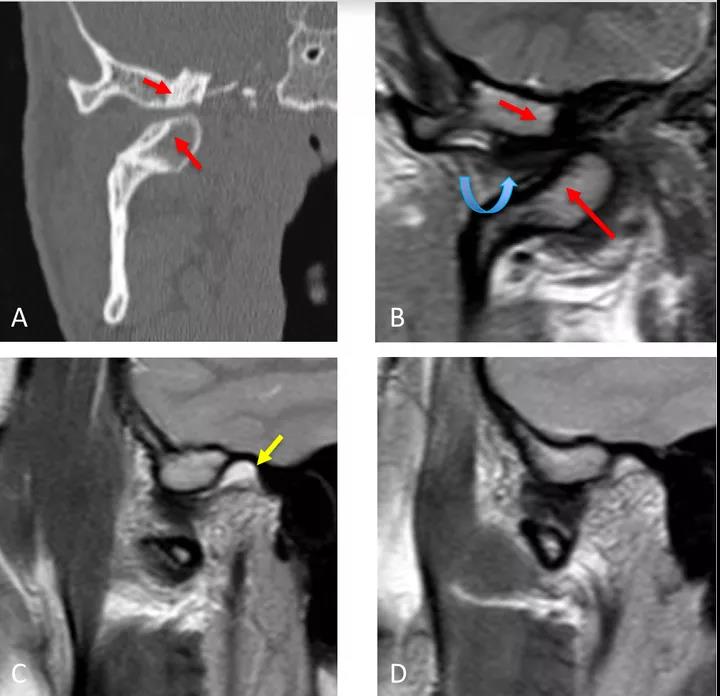

病例二:顳下頜關(guān)節(jié)脫位

冠狀面CT圖(A)和冠狀面PDWI圖(閉口)(B):顯示由于先前骨折導(dǎo)致的下頜髁突內(nèi)側(cè)移位的顳下頜關(guān)節(jié)脫位,與骨折畸形愈合、前上髁和后顳嵴硬化(紅色箭頭)相關(guān)。關(guān)節(jié)盤位于下頜骨髁突和顳突之間,失去正常的形態(tài)(彎曲箭頭)。

矢狀位T2WI圖(閉口)(C):顯示正常位置的下頜骨髁突及關(guān)節(jié)積液(黃色箭頭)。

矢狀位PDWI圖(開口)(D)顯示髁突明顯偏移。